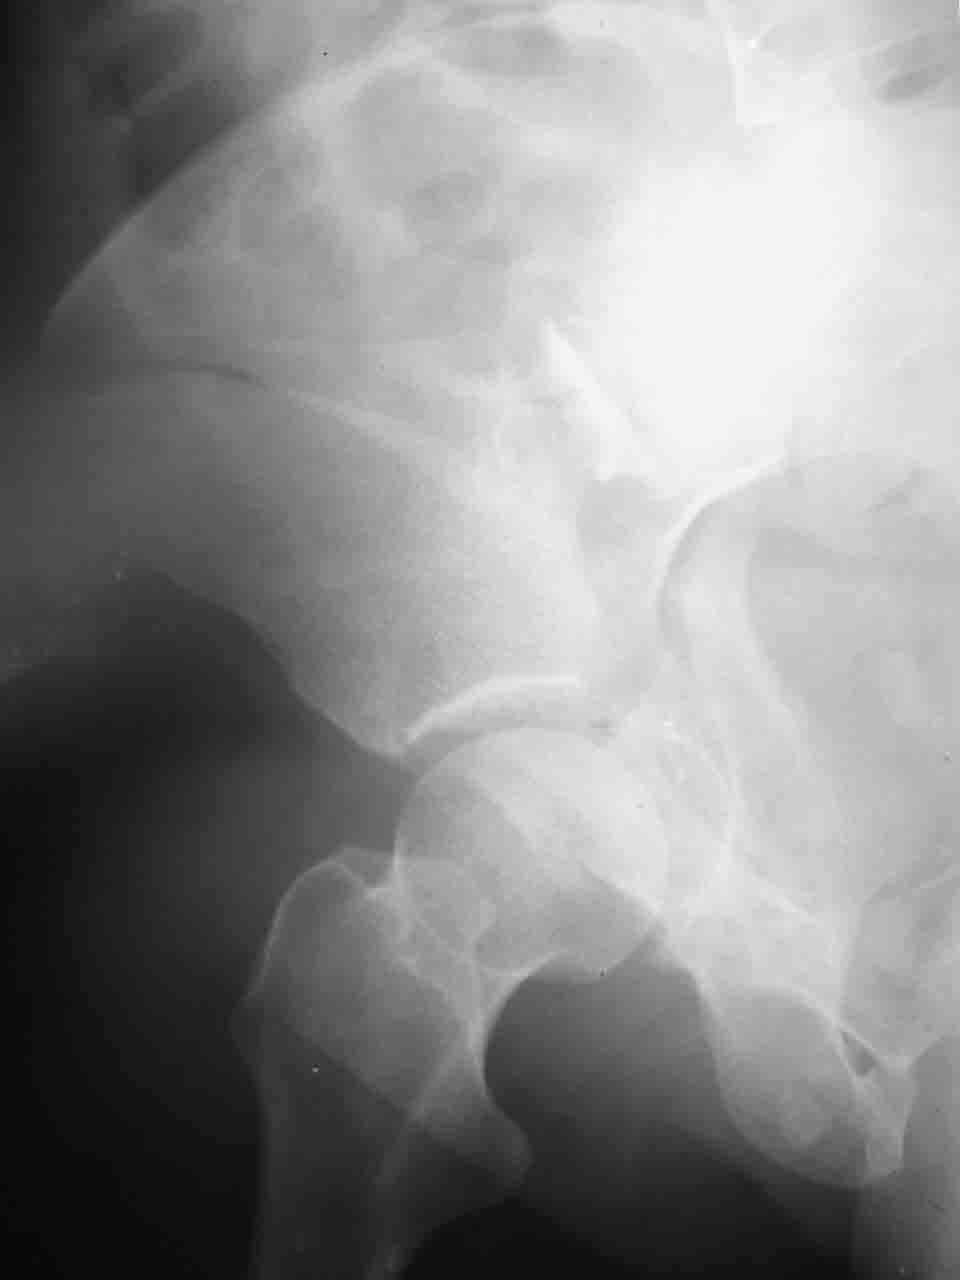

Логика подсказывает, что все-таки лучше иметь анатомически полноценную впадину, хотя ранее упоминалось состояние вторичной конгруэнтности и одно наблюдение у меня есть, когда у больного с полностью нарушенной анатомией впадины и подвывихом головки бедра кзади и кверху боли отсутствовали при относительно достаточном для стиля жизни больного объёме движений. Но это только одно наблюдение и кроме перелома впадины у этогобольного была и тяжелая ЧМТ в анамнезе. Основываясь на формулировке структуры ацетабулюм Э. Летурнеля - как перевернутой буквы Y, впадина для полноценной функции сустава должна иметь сферичность, соответствующую размеру головки бедра и если один из компонентов в дефиците, то функциональные последствия рано или поздно проявятся.

Интерес к реконструкции вертлужной впадины у меня появился довольно-таки давно, но до недавнего времени как-то не ощущалась готовность к практической реализации, а местный подход достаточно консервативен - перелом срастется,

а далее будет видно. Такую точку зрения я не разделяю, поэтому через конференции,ортофорум и свои случаи пытаюсь практически и теоретически *продвинуть* для себя тему реконструкции вертлужной впадины.